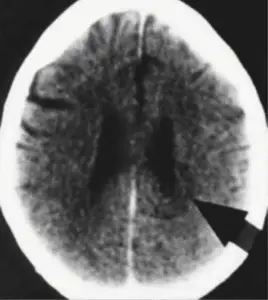

If one found glia accumulations in the brain in the brain-computer-tomogram, since this existed, which were also well stainable with contrast medium, then the diagnosis was usually certain: brain tumor!

There remained controversy about the so-called ring artifacts, which exist but are seen only once in every 100th patient and are regarded by me as Hamer Focus in target configuration, i.e., the conflict-active phase. The alleged ring artifacts denied by me, with few quite clear exceptions, quite vehemently, or are just claimed as HHe in shooting target configuration, are always denied by the radiologists as facts and just considered artifacts, i.e., art products of the apparatus.

In DHS, the responsible relay center in the brain is marked, and a so-called shooting target configuration marks it. Around the center of this relay, sharp circles, we also say concentric circles, are formed, which look like shooting targets. “Shooting target” means the Hamer Focus is in the conflict-active phase.

Hamer Focus in the conflict-active phase, namely the shooting-disc configurations, has always been misinterpreted as artifacts of the apparatus. If they got edema later and became so-called brain tumors, the radiologist usually did not bother to determine that this supposed brain tumor had been visible earlier as a shooting target configuration, i.e., as a Hamer Focus in the conflict-active phase. Since the SIEMENS company and I signed the paper cited at the end of this chapter, the alleged artifacts’ discussion should finally be over. They were facts: I.e., the shooting targets signified the conflict-active phase in a particular relay or relay group of the brain.

In a DHS, the “responsible relay center” in the brain is marked, and thus Hamer Focus in shooting target formation. As soon as we see this shooting target configuration in a specific relay in the CCT, we know that a special program runs in this relay. I.e., the organism has been caught on the wrong foot in this conflict, brain and organ area, and has switched on a special program.